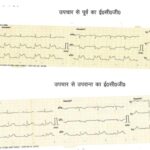

- Treatment of patient suffering from Acute Myocardial infarction via Thrombolysis mechanism using Streptokinase started in RMC Jalaun.